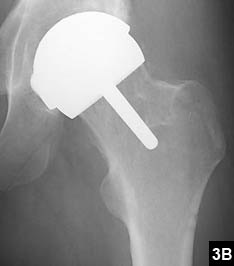

An uncommon, but useful indication for hip resurfacing is for patients with proximal femoral deformity, in whom a total hip can be difficult if not impossible (Figure 1). More commonly, suboptimal anatomy is an issue, as with patients in whom even the smallest stem requires reaming, which puts patients at long-term risk for stem fracture (Figure 2). Conversely, a large canal presents problems for implanting a cementless stem (Figure 3).

Figure 3: Preoperative templating reveals the largest cementless stem would be necessary to obtain a press-fit (A). Postoperative radiograph shows successful hip resurfacing, which allowed the patient to return to competitive hockey (B).